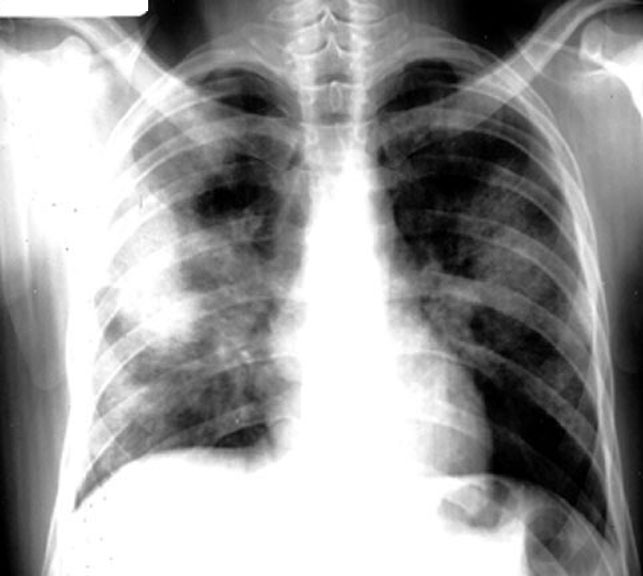

Sarcoidosis / Alveolar Form

• Bilateral

• Soft fluffy lesions

• Segmental

• Coalesce

• Air bronchogram